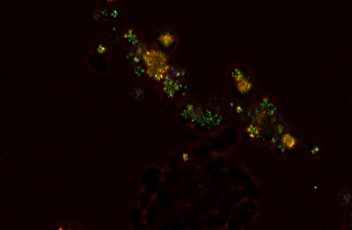

?落射熒光

小巧的落射熒光附件中采用了Ci系列的專用噪聲消除裝置,拍攝到的熒光圖像明亮、對比度和信噪比(S/N)高。濾光塊轉盤最多可以容納四個濾光塊,更換非常簡單。濾光塊的名稱和位置位于附件前面的熒光標簽上,在光線暗淡的房間內也可輕松識別。濾光塊中的濾光片或分色鏡可以輕松更換,以靈活搭配各種組合。